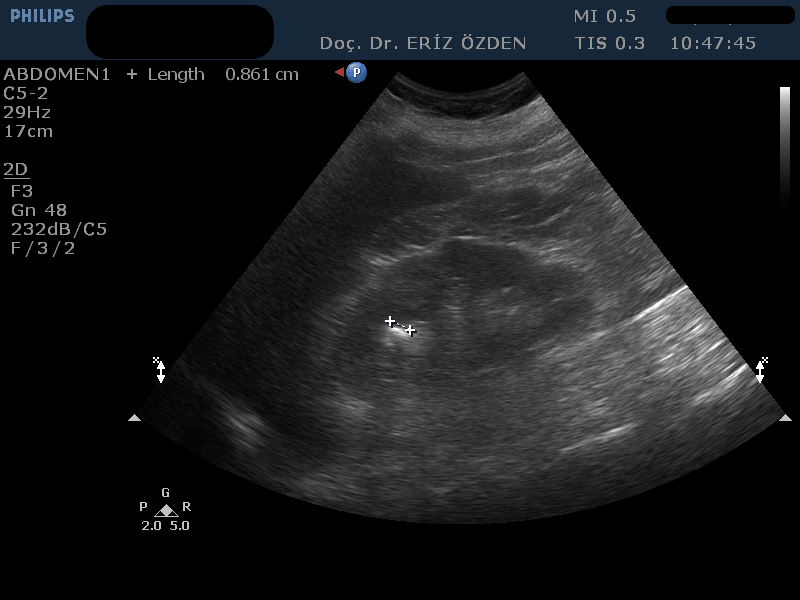

Böbrek Taşı Nasıl Tespit Edilir? Böbrek taşı ağrısı, tıpta bilinen en şiddetli ağrılardan birisidir. Genelde böbrek içinde sabit duran taşlar şiddetli ağrıya neden olmaz. Ancak taş böbrekten çıkıp, üreter adı verilen idrar kanalına girdiğinde şiddetli ağrı başlar. Kolik ağrısı denilen bu durumda ağrıyla birlikte bulantı, kusma gibi bulgular ve idrarda kan da görülebilir. Ayırıcı tanı öncelikle görüntüleme yöntemleriyle yapılır. Ağrının kaynağı idrar yollarındaki taş mı, taş varsa yeri neresi ve büyüklüğü nedir sorularının cevapları tedavide çok önemlidir. Bu bilgiler düz röntgen filmi, Bilgisayarlı Tomografi ya da Ultrason ile elde edilir. Böbrek taşlarının hepsi röntgen filminde görülmez. Bu tip taşlar kimyasal içerikleri nedeniyle röntgen ışınlarına geçirgendirler ve filmde hiç görülmezler. Direk röntgen filminin diğer bir dezavantajı ise hastanın az da olsa zararlı iyonize radyasyona maruz kalmasıdır. Ultrason ise hiç zararlı radyasyon içermeyen bir yöntemdir ve kimyasal içeriğinden bağımsız olarak hemen tüm böbrek taşları görülebilir. Ultrasonla izlenemeyen böbrek taşları boyutu 2 mm’den küçük olanlardır. Bunlar kristaloid odağı ya da kum olarak adlandırılır ve ancak idrar tahlillerinde mikroskop incelemesinde görülür. Böbrekten çıkıp kanala giren taşlarda ultrasonla hem taşı, hem de röntgende görülemeyen idrar kanalı genişlemelerini izleyebiliriz. Böylece, düşmesi geciken taşlarda, böbreğin durumuna göre ne kadar bekleneceğine karar verilebilir. Ultrasonun tek dezavantajı, bağırsak gazı çok yoğun olan hastalarda, kanal içindeki taşları görmenin zorluğudur. Üreter adını verdiğimiz kanalın içindeki taşlar, bağırsak gazlarının arkasında kaldıysa, ultrasonla görülemeyebilir. Uluslararası çalışmalarda üreter taşlarının ultrasonla görülebilme oranı %50 olarak bildirilmektedir. Ancak, ultrasonu yapan doktorun tecrübesi ve uzun zaman ayırarak sabırla taşı araması, kanaldaki taşların görülme oranını ciddi anlamda yükseltmektedir.

Üreter taşlarını en net gösteren yöntem ise Bilgisayarlı Tomografidir (BT). Hemen hemen tüm üreter taşları BT ile izlenebilir. Ancak tomografi çekimi sırasında hasta düz röntgen filminden daha da yüksek oranda zararlı radyasyon alacaktır. Bu yüzden, böbrek taşı ve üreter taşı varlığından şüphelenilen hastalarda ilk olarak Ultrason incelemesi yapılması, eğer taş ultrasonla görülemiyor ise düz röntgen filmi ya da BT’nin tercih edilmesi önerilmektedir.